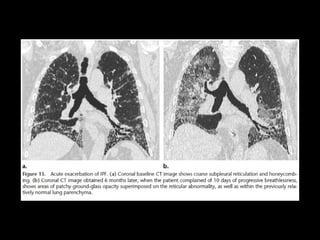

• Complicaciones:

• Exacerbación, DAD

UIP TC • Fibrosiscon áreas normales. • Disminución de volumen pulmonar • Opacidades reticulares • Vidrio esmerilado • Predominio en regiones basales y subpleurales • Distorsión arquitectónica con bronquiectasias por tracción secundaria a fibrosis. • Panal de abejas (2-20mm) • Linfoadenopatías mediastínicas pequeñas.

DD UIP CT •AR, Esclerodermia (esófago dilatado) • Asbestosis ( derrame pleural, bandas parenquimatosas) • Neumonitis por hipersensibilidad crónica: fijarse en signos de atrapamiento aéreo, Respeto de bases o cuando hay nódulos centrolobulillares. • Sarcoidosis terminal: fibrosis en segmentos posteriores de lóbulos superiores o perihiliar, o nódulos perilinfáticos. • NSIP • Complicaciones: • Exacerbación, DAD • Cáncer pulmonar 10-15% bases